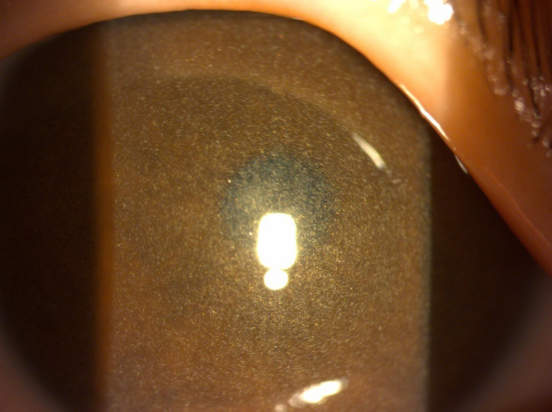

胱氨酸贮积症(cystinosis)是指由于CTNS基因突变,导致溶酶体膜上L-胱氨酸转运蛋白缺乏,使得胱氨酸在溶酶体内蓄积,导致眼、肾脏、心脏、腺体等多器官功能障碍的疾病。该病为一种罕见的常染色体隐性遗传疾病。文献报道该病的发病率1/115000~1/192000。国内尚无相关报道。我们报道了一例典型的胱氨酸贮积症病例。

对于该病,早期诊断、治疗是改善预后的关键,我国目前对于该病的认识相对有限。我们复习了相关文献,并在文中提出所有婴幼儿Fanconi综合征及不明原因的进行性肾功能下降的患者均应该注意除外胱氨酸贮积症的可能。眼裂隙灯检查为最方便的筛查手段。该文章发表于《Archives of Disease in Childhood》期刊上,该期刊为欧洲儿科学会及皇家儿科医学会会刊,该文章的发表对于儿科同道进一步了解该病,提高该病的诊疗水平具有重要意义。

典型角膜胱氨酸结晶(6岁女童,肾病型,未规律治疗)